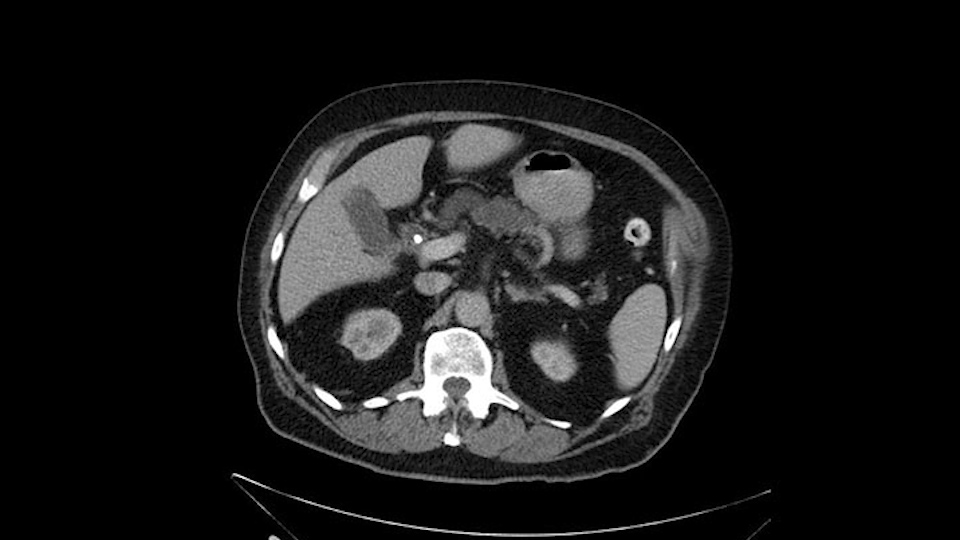

He has no liver metastases or obvious metastatic disease. On reviewing his CT scan, he has normal vascular anatomy; he has no involvement of the portal vein by the looks of it, or the superior mesenteric vein.

He has normal arterial anatomy: no accessory or replaced right hepatic artery, which is important because sometimes the right hepatic artery can come behind the neck of the pancreas and you have to be careful of that in a Whipple dissection.

So when I’m assessing a CT scan for a presumed periampullary cancer, either pancreatic or otherwise, of course you want to look at some of the big picture items: metastatic disease, invasion of the mesentery at the root. I’m not looking for them here because it's a small tumor and we’re reliant on the radiologist to report these so I usually look at the report.

Looking at the C.T. scan, the most important thing to determine is, of course, does the patient have any evidence of metastatic or disseminated disease or locally advanced disease? The imaging shows dilated intrahepatic biliary tree but I don't see any signs of liver metastasis. As would be expected with a ampullary lesion there's no evidence of major visceral vessel invasion. So this patient would look to me to be a candidate for pancreaticoduodenectomy or Whipple procedure.